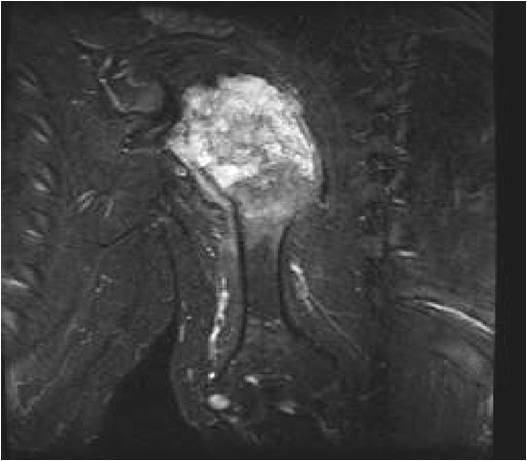

- MRI

- Lobulated margin

- Marked increased intensity long TR images

- Calcified chondroid – low intensity all sequences

MRI:

- Lobulated margin (Lobular Growth Pattern)

- T2 Weighted Images: High Signal Intensity

- High water content shows as high signal on T2 weighted images

- Calcifications will be low signal

- There should never be any cortical destruction nor a soft tissue component. If this exists then the tumor must be a chondrosarcoma.

- Endosteal scalloping and cortical expansion is acceptable for phalangeal tumors. In most benign long bone cartilage tumors there is minimal endosteal scalloping but there should be no cortical expansion nor thickening. There should be no cortical destruction and no soft tissue component associated with an enchondroma. Cortical destruction, periosteal thickening, cortical expansion and a soft tissue component indicates a chondrosarcoma of the long bone.